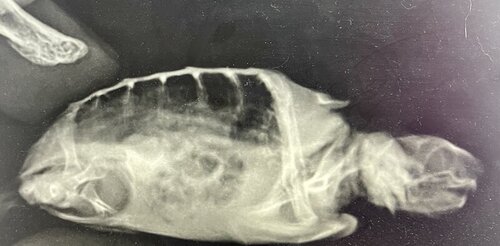

Покажите пожалуйста врачам снимок

наша доктор не может понять, что за образование круглой формы

Сказали, что кишечник загазован